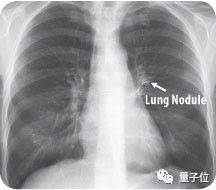

目前,传统检测方法仍无法发现肺部40毫米大小的结节,因此肺癌患者死亡率高达90%。惊喜的是,Enlitic开发的系统能发现小于5毫米的结节,使患者的生存率能增加10倍。

△ 图中箭头所指为肺结节(Lung Nodule)